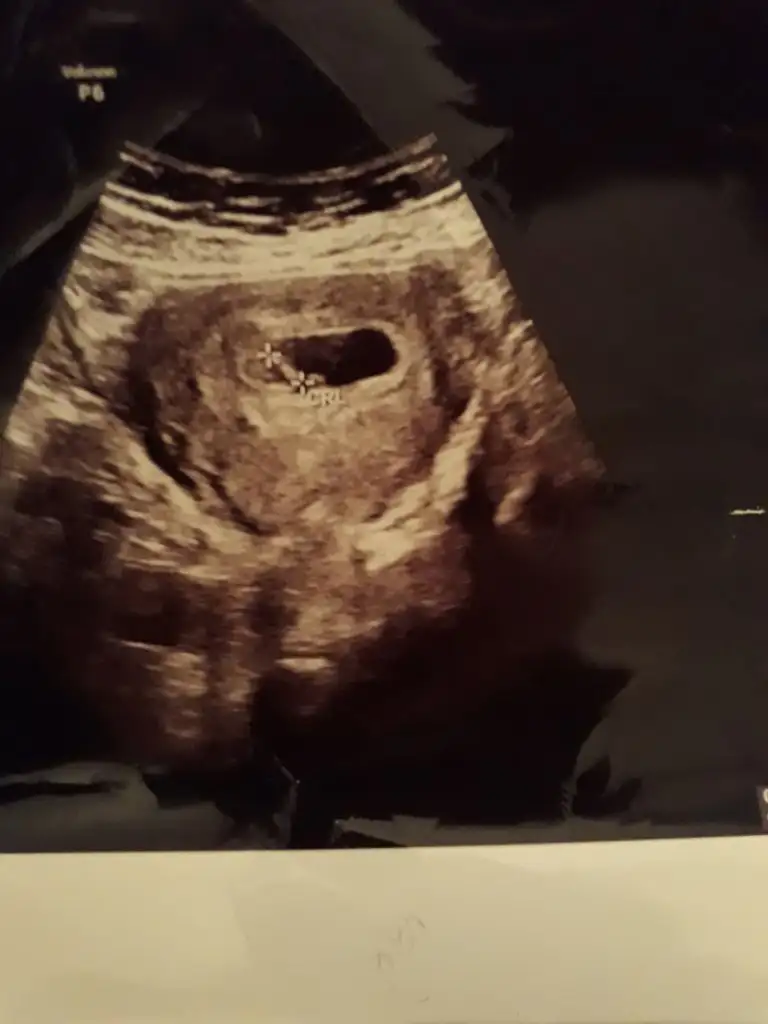

Benimki en son 8 haftalikti :)Bulunuruz canım kesin olmamakla beraber

Varmı görüntüsü kuzumBenimki en son 8 haftalikti :)

Var atayım canımVarmı görüntüsü kuzum ☺

Buna göre erkek tabiki en iyi 11 12 13 haftalar olmalıEki Görüntüle 2682785